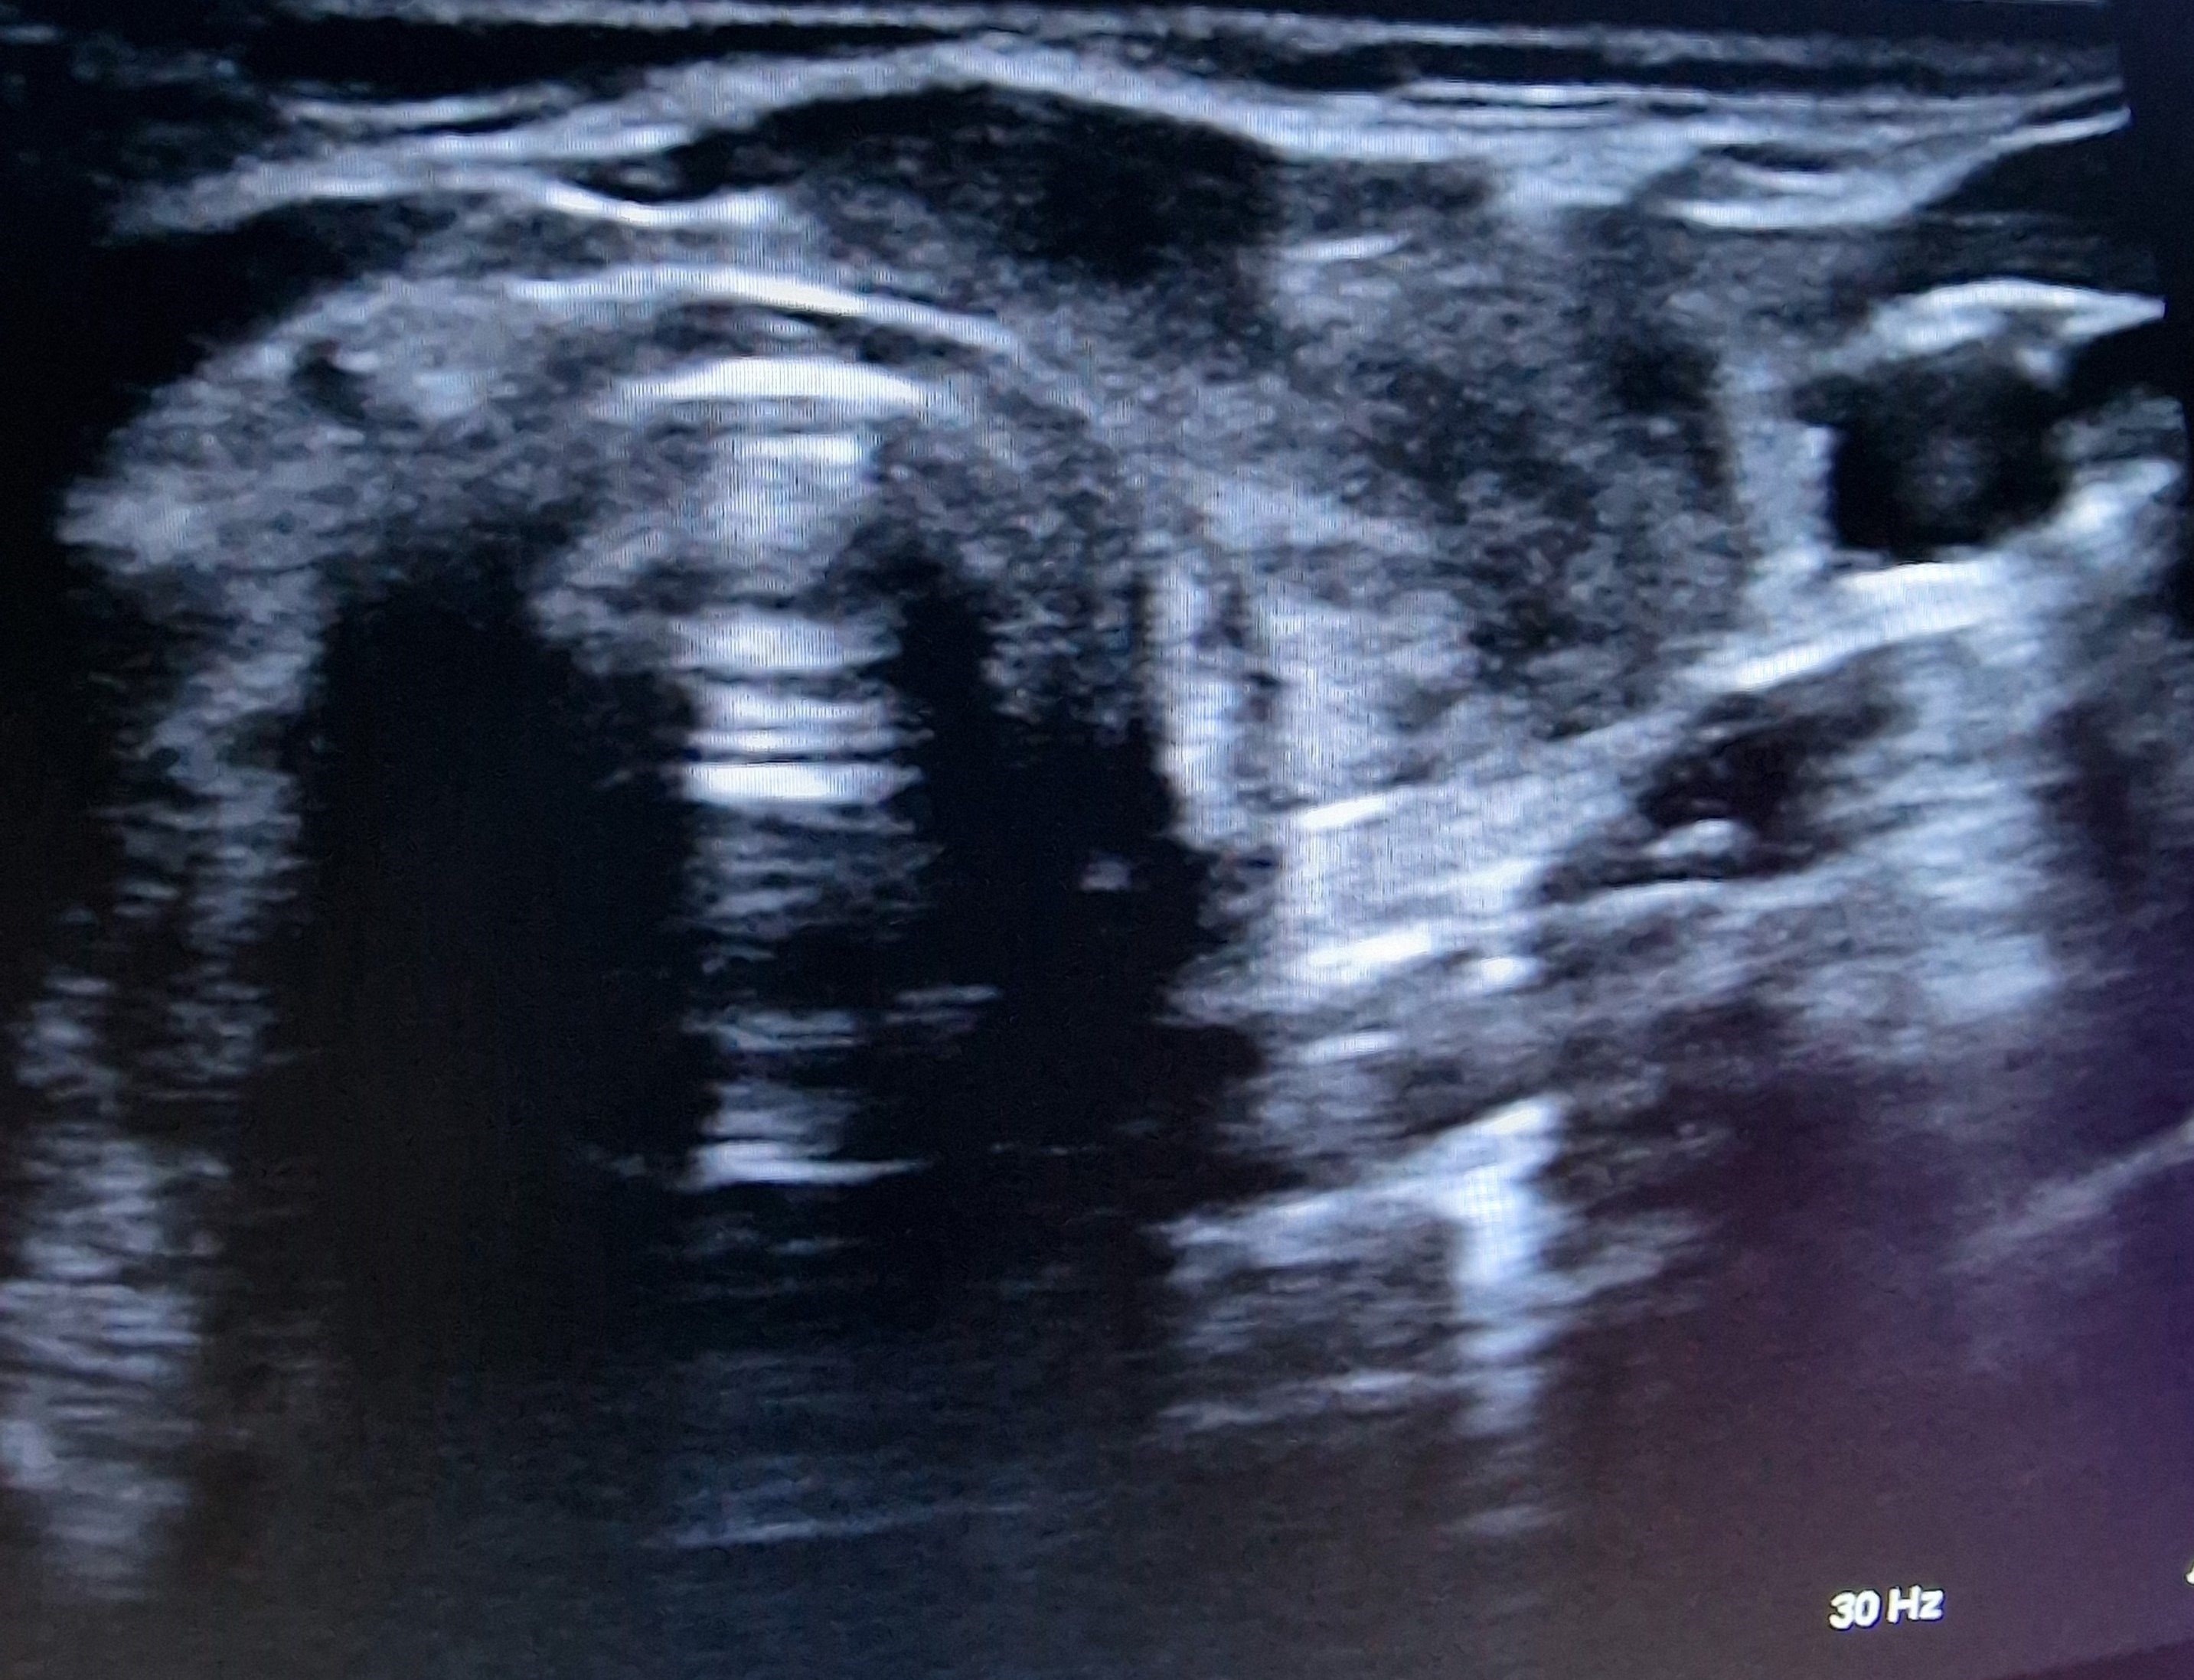

Ecografía cervical: tiroides de ecogenicidad heterogénea con áreas hipoecogénicas y ausencia de vascularización de éstas, Lóbulo Tiroideo Derecho 20 x 14 mm con nódulo < 10 mm no maligno e izquierdo 16 x 12 mm.